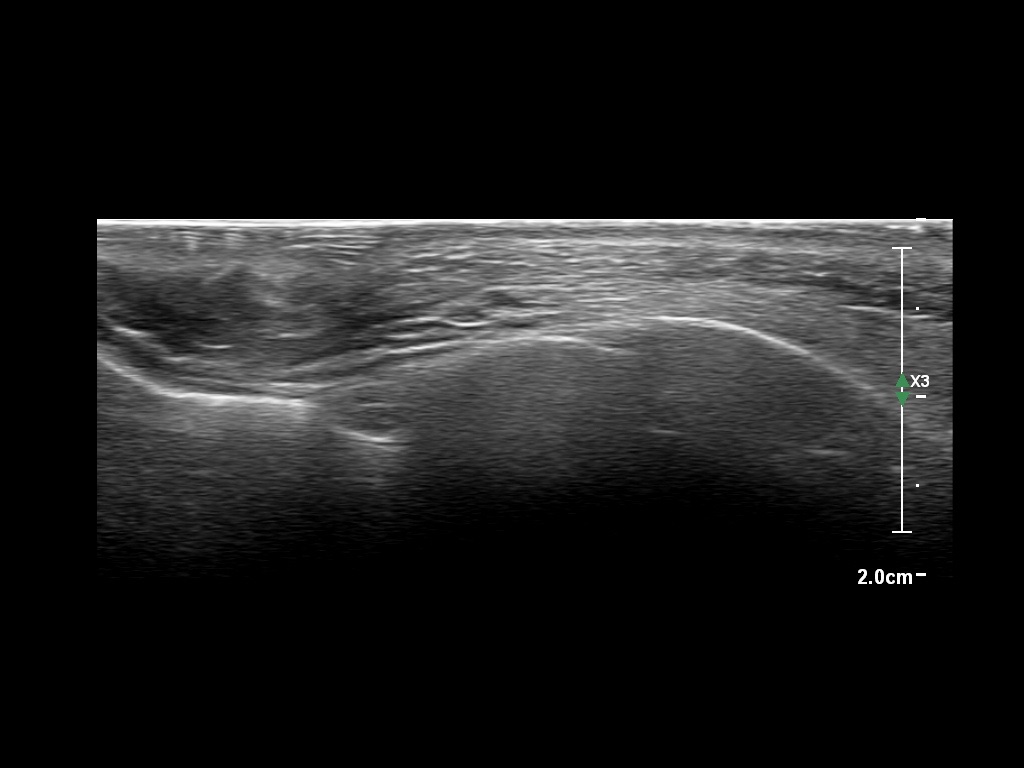

Study the first image to recognize the different layers. If you are sure about the layers, swipe to the second image to view the answer (if applicable).